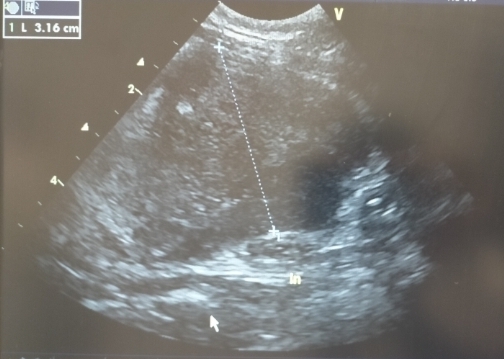

10日前に気になる腫れがあると言われていた腸に3cm越えの異物がゴロゴロ出来ていて、ほぼ間違いなく腫瘍ですと…それも増殖スピードが異常に早いので、このままだと2~3日で食べられなくなり、1週間も持たないかもしれない…

🔺最大サイズだった時の腫瘍

10日前の診察時には存在すらしなかったのに…凄まじい成長スピードでした💦